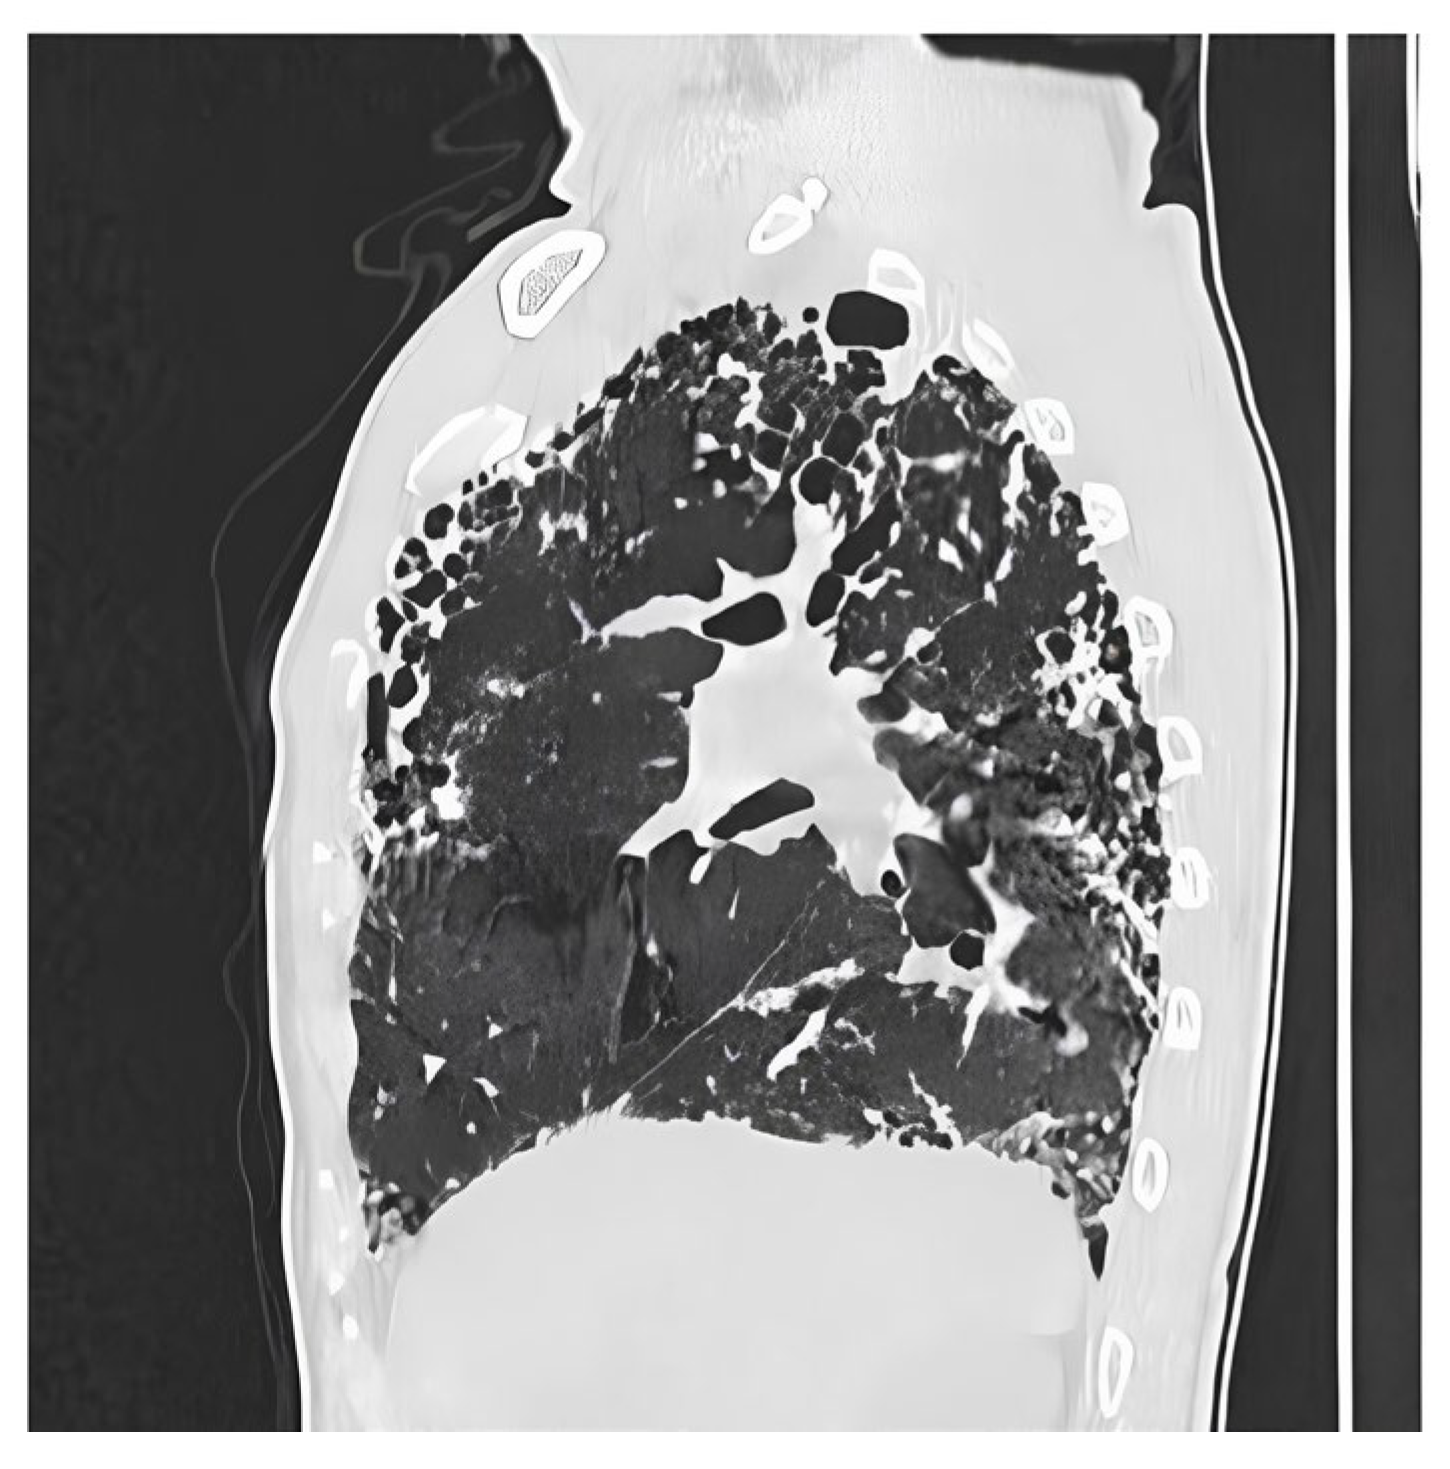

- Gaillard, F. Idiopathic Pulmonary Fibrosis. Available online: https://radiopaedia.org/cases/idiopathic-pulmonary-fibrosis-5?case_id=idiopathic-pulmonary-fibrosis-5 (accessed on 1 June 2025).